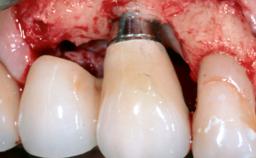

Reconstructive Treatment of a Peri-Implantitis Defect at an Implant in a Mandibular Molar Site

In this case, Mario Roccuzzo utilizes surgical bone regeneration treatment around implant 46 using a bone graft substitute and a connective tissue graft to resolve peri-implant inflammation, reduce the probing depths, and prevent further progression of disease.